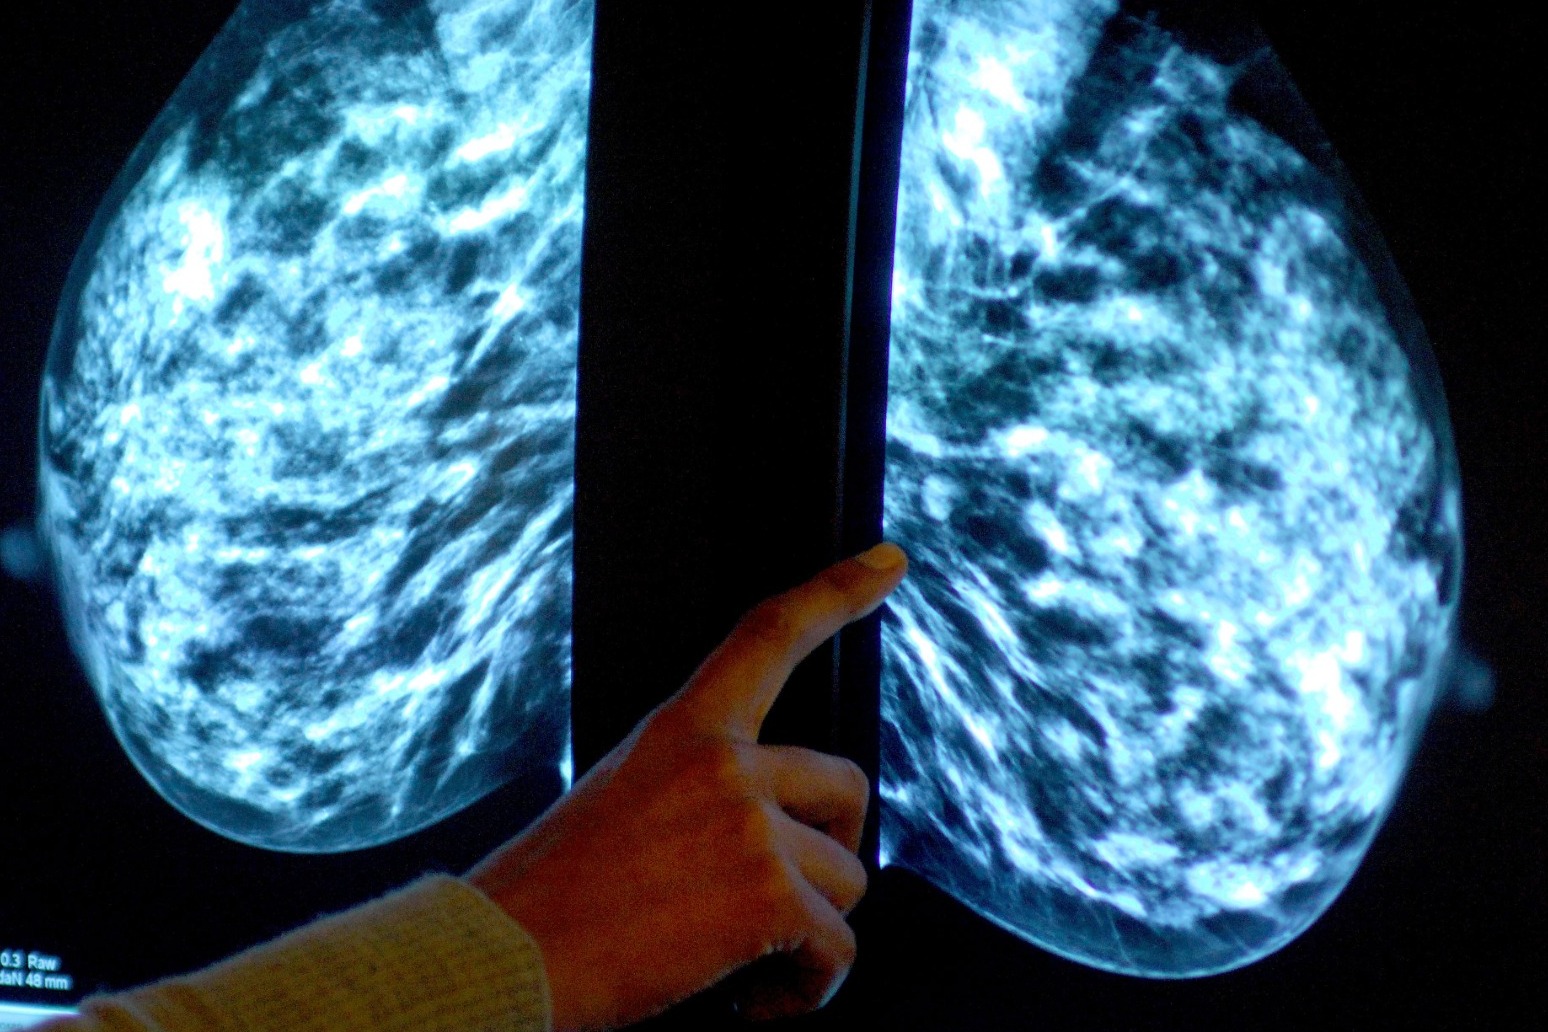

It comes as Prime Minister Rishi Sunak hailed a new artificial intelligence (AI)-powered medical trial which “promises to improve the accuracy and speed” of breast cancer diagnosis.

A partnership between the NHS and South Korean firm Lunit uses the Korean company’s image-reading AI technology to help human radiologists in the process of analysing and assessing mammograms.

The leaders said: “We all know how vital early detection is – so just imagine what improvements here could mean for millions of women and their families.”